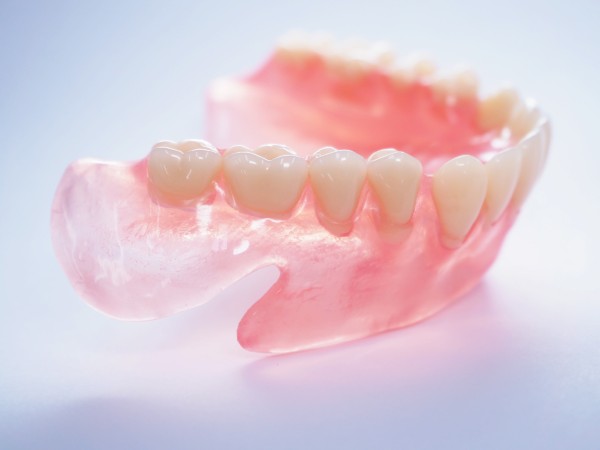

ノンクラスプデンチャー

ノンクラスプデンチャーは、金属のバネを使用しない入れ歯です。歯ぐきに近い自然な色の素材で作られており、装着してもほとんど目立ちません。軽くてフィット感が高く、装着時の違和感が少ないのが特徴です。金属アレルギーが気になる方にも安心で、見た目と快適さの両立を求める方に適しています。笑ったときにも自然な印象を保てるため、審美性を重視する方にも人気の高い義歯です。